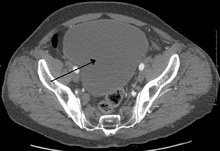

| Urinary retention with greatly enlarged bladder at CT. | |